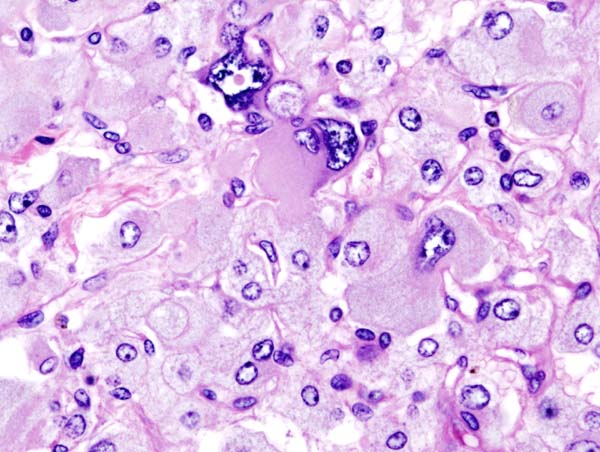

248. Potter LR, Yoder AR, Flora DR, Antos LK, Dickey DM (2009). "Natriuretic peptides: their structures, receptors, physiologic functions and therapeutic applications". Handb Exp Pharmacol 191 (191): 341–66. http://www.springerlink.com/content/u648j605872u4360/ .

295. KGH Histopathology of adrenal pheochromocytoma. Adrenectomy specimen. http://en.wikipedia.org/wiki/File:Adrenal_pheochromocytoma_(3)_histopathology.jpg .